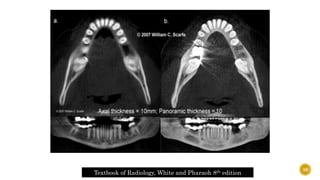

Textbook of Radiology, White and Pharaoh 8th edition 11

 Also knownas the “traumatic zone”  1. BONE  Part of the anterior maxilla is a protruding alveolar process with thin labial and thick palatal cortical plates covering and protecting upper front teeth.  Evaluate the deficiency 61